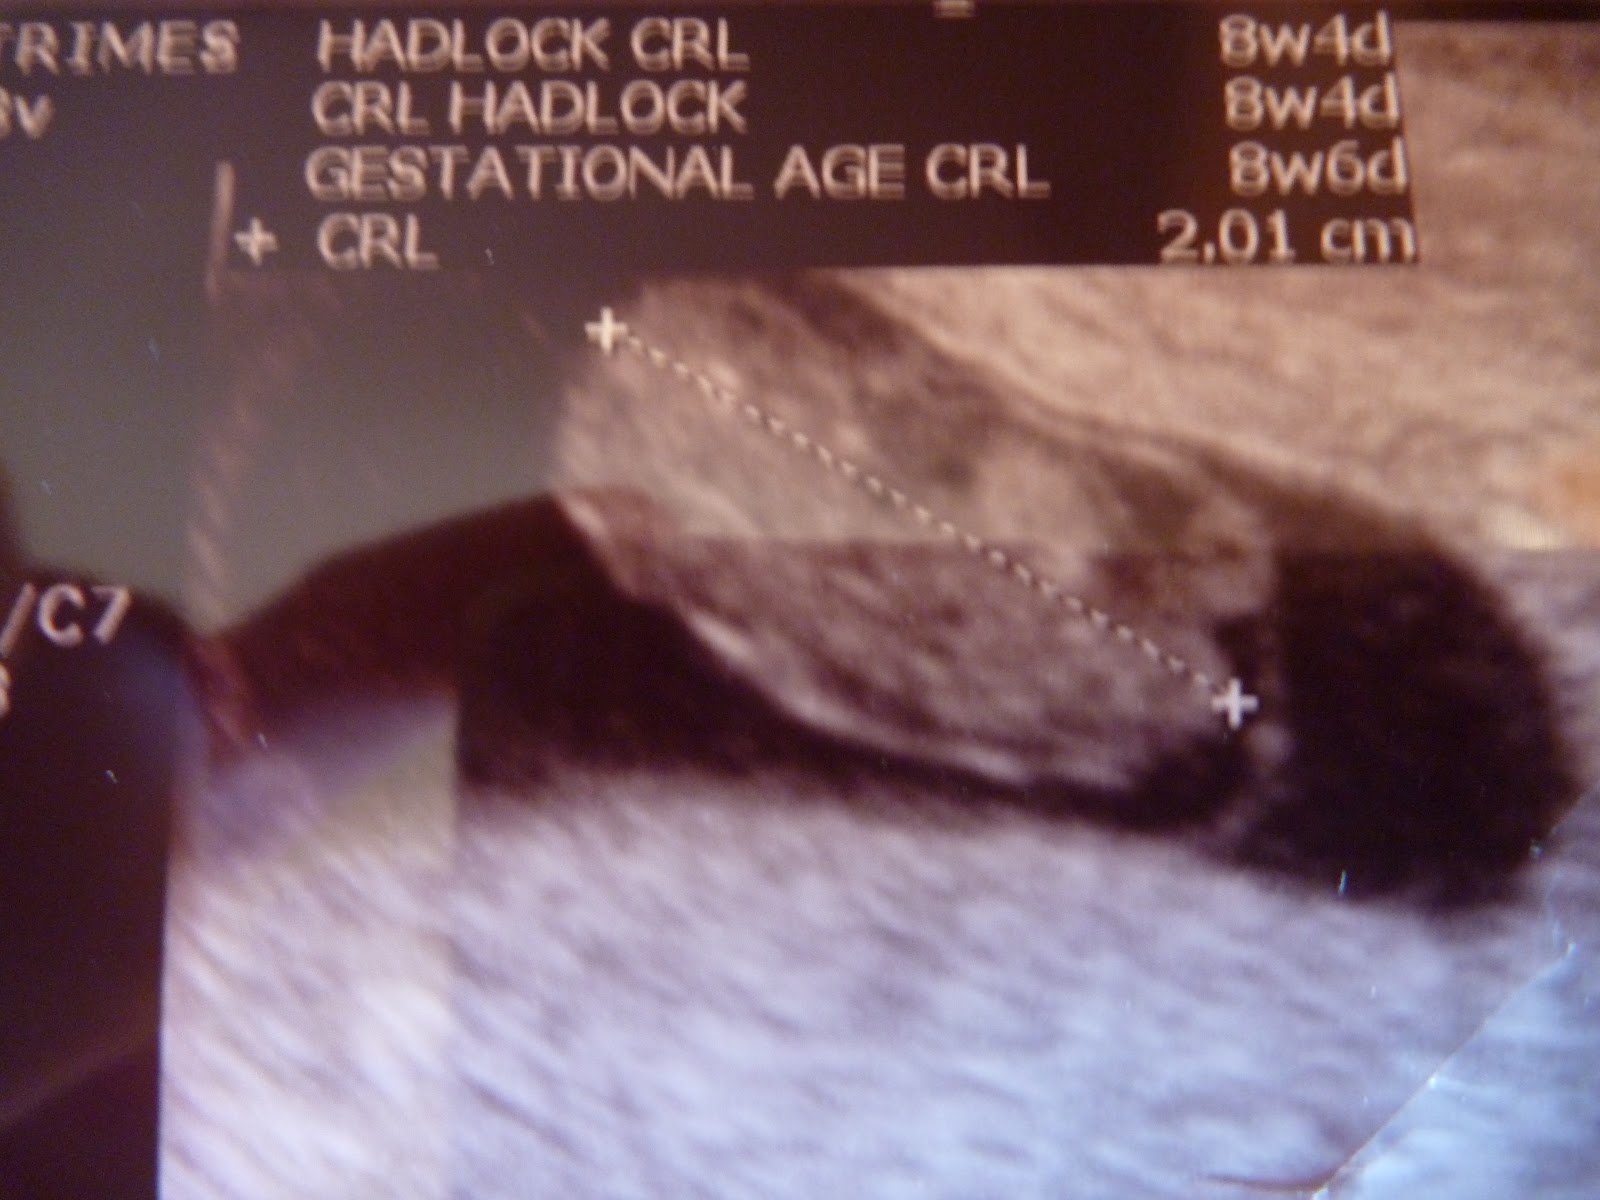

Kh. Patty’s story: Constantine

Story of spontaneous miscarriage at 8 weeks